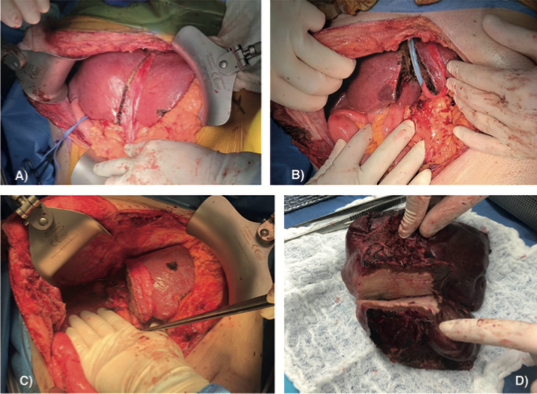

Gabriela Susana Ochoa Suazo, Nicolas Jarufe Cassis, Martin Dib Marambio

|

|

|